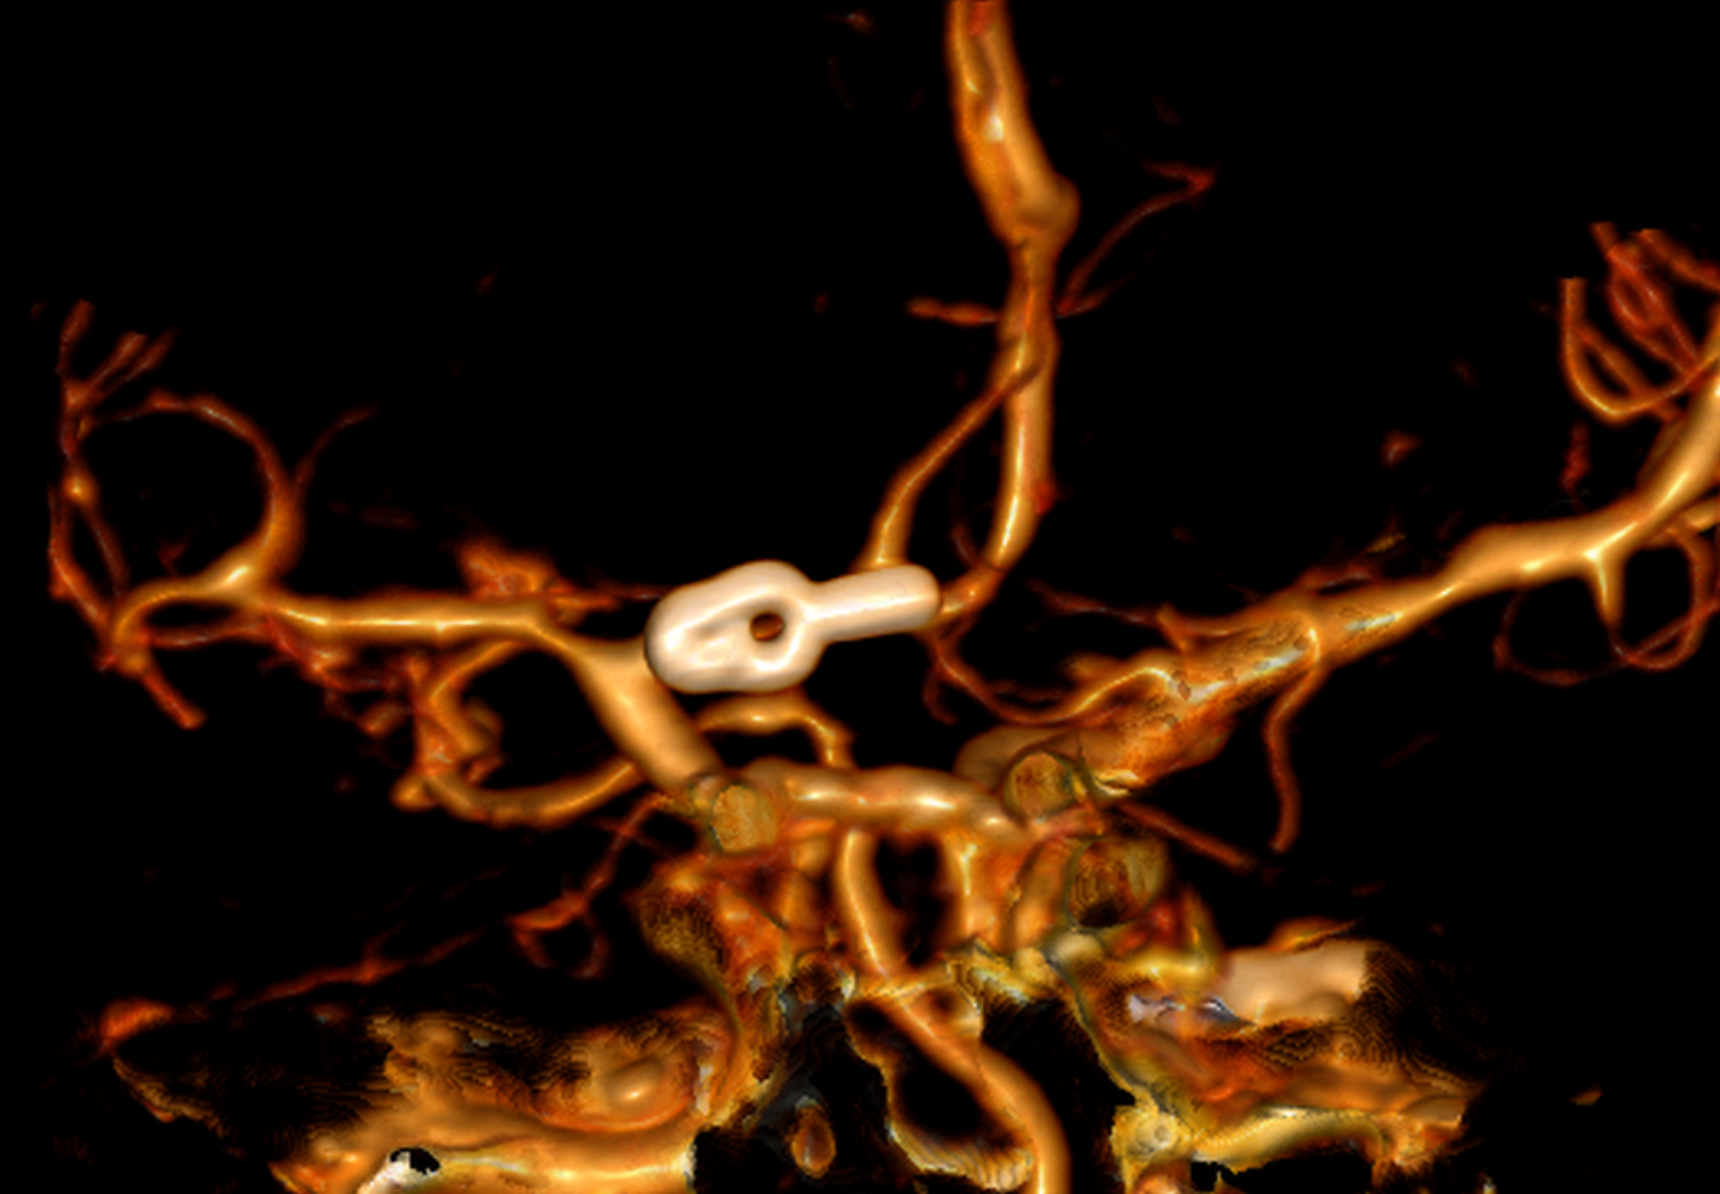

El patrón de hemorragia típico que se observa después de la ruptura de un aneurisma. La forma y la ubicación del aneurisma pueden predecir su comportamiento y también determinar qué opción de tratamiento es probable que sea la mejor. Alternativamente, si el aneurisma representa un bajo riesgo de ruptura o un alto riesgo quirúrgico, podemos optar por seguirlo con imágenes en serie. La intervención está diseñada para detener el flujo de sangre hacia el aneurisma, eliminando así el riesgo de hemorragia. Se puede realizar de forma endovascular rellenando el aneurisma desde dentro («coiling» endovascular), o mediante técnicas microquirúrgicas abiertas («clipaje»).

Aneurisma recurrente visto cerca de clips

Angiografía cerebral 3D que muestra un aneurisma